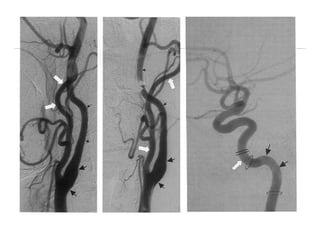

ARTÉRIA CARÓTIDA INTERNA

• A ACI se origina da ACC no nível C3-C4 ou C4-C5.

• Inicialmente possui dois segmentos, o bulbo carotídeo

e o segmento cervical (C1).

• Situa-se medialmente à ACE a medida que ascende no

pescoço, embora origina-se lateralmente a esta; é

anterior e mediamente a VJI.

• Não apresenta ramos cervicais.

Segmetação da ACI

• C1: Cervical

• C2: Petrosa

• C3: Cavernosa

• C4: Supraclinoidéa

• Segmento oftálmico

• Segmento comunicante

• Segmento coróideo

Artéria carótida cavernosa

• Está recoberta pelo gânglio trigeminal.

• Joelho posterior (mais medial) e joelho anterior (mais

lateral).

• O VI nervo é inferior e lateral a ela, no interior do seio.

Os III, IV, V1 e V2 estão na parede lateral do seio

cavernoso

• Emite três ramos importantes: tronco posterior (artéria

meningo-hipofisária), tronco ínfero-lateral e artérias

capsulares (pequenas e inconstantes).